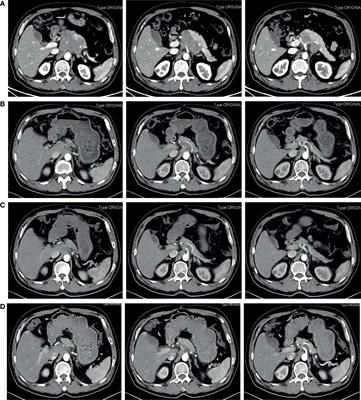

Original Research

Published on 03 May 2023

in Cancer Imaging and Image-directed Interventions